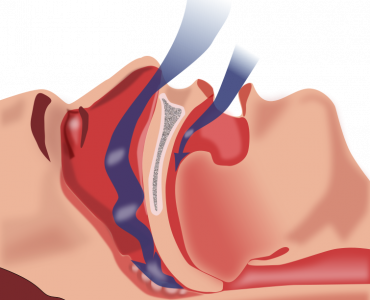

Devamını OkuHorlama Ve Uyku Apnesi Tedavisi

Horlama ve uyku apnesi tedavisi kişinin hayat kalitesini arttıran horlama protezleri ile hızlı ve etkili çözüm sunan bir uygulamadır.